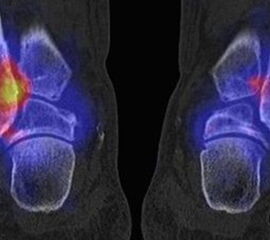

Die Abbildungen 4.2.a bis d zeigen den typischen Aspekt einer talacalcanearen Coalitio. Es besteht nur eine linksseitige, symptomatische Coalitio talocalcaneare (4.2.a und c); das 35 Tage zuvor angefertigte MRT zeigt keine auffälligen Signalveränderungen (4.2.b und d).

Abbildung 4.3. zeigt die Ursache für rechtsseitige Sprunggelenksbeschwerden bei einem Patienten mit talocalcanearen Coalitionen: nur die osteochondrale Läsion an der distalen rechten Tibia ist die Ursache des Schmerzes. Die bilateralen talocalcanearen Coalitionen sind asymptomatisch.